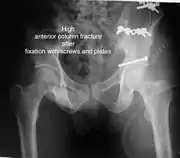

High anterior column fracture after fixation with screws and plates

High anterior column fracture 3 D CT scan picture

| Anterior column | This fracture is uncommon, typically occurring when the injuring force is applied from the side, against the greater trochanter of the femur bone, as in a fall on the side or being hit on the side. Depending on the location, the fractures are described as very low, low, intermediate and high anterior column fracture. | Anterior column + posterior hemi transverse | In this variety of fractures, the posterior or ilio ischial column is broken as a transverse fracture, while the anterior or ilio pubic column is broken into multiple pieces. Part of the weight-bearing dome in this variety of fractures is still attached to that part of the iliac wing, which forms part of the iliac joint. This type of injury has to be differentiated from both column fractures, where the weight-bearing dome is a floating piece not attached directly to the bone-forming sacroiliac joint.

The final management depends on the size of the fragment(s), stability and congruence of the joint. In some cases traction for six to eight weeks may be the only treatment required; however, surgical fixation using screw(s) and plate(s) may be required if the injury is more complex. The latter treatment will be called for if bone fragments do not fall into place, or if they are found in the joint, or if the joint itself is unstable.